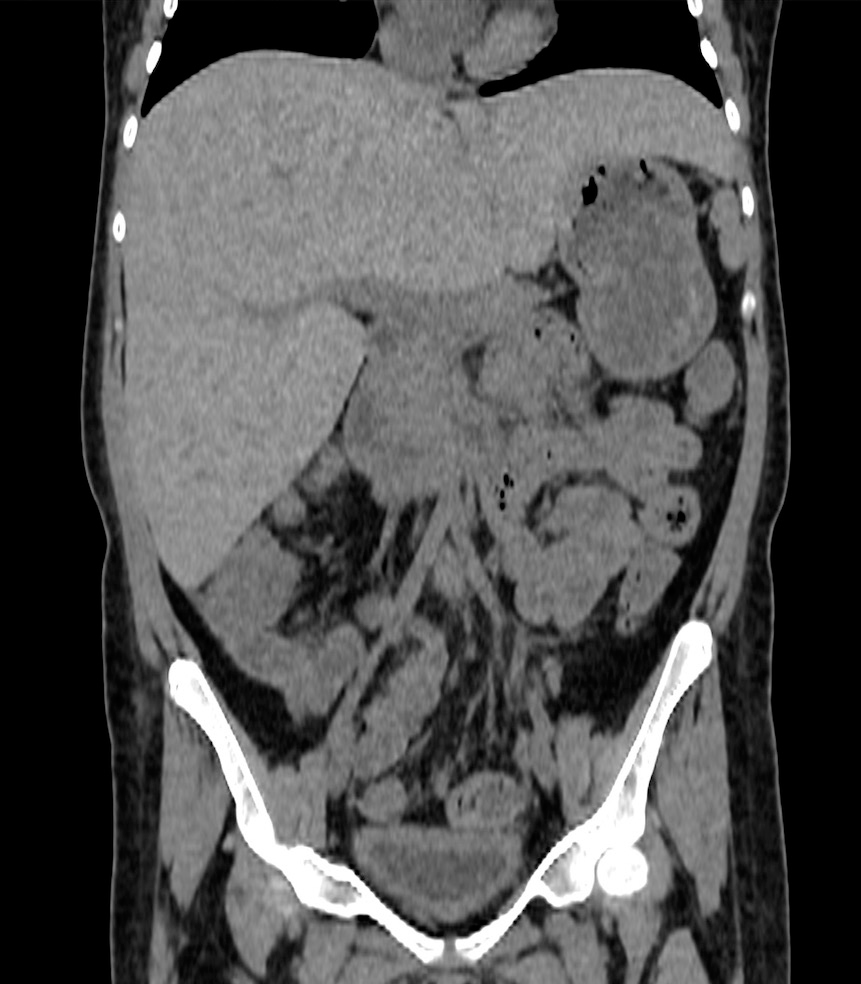

Tomografía computada (TAC) sin contraste que evidencia moderada hepatomegalia de 18 cm en su eje longitudinal (Figura 1).

Figura 1: Corte coronal de escáner sin contraste. Discusión